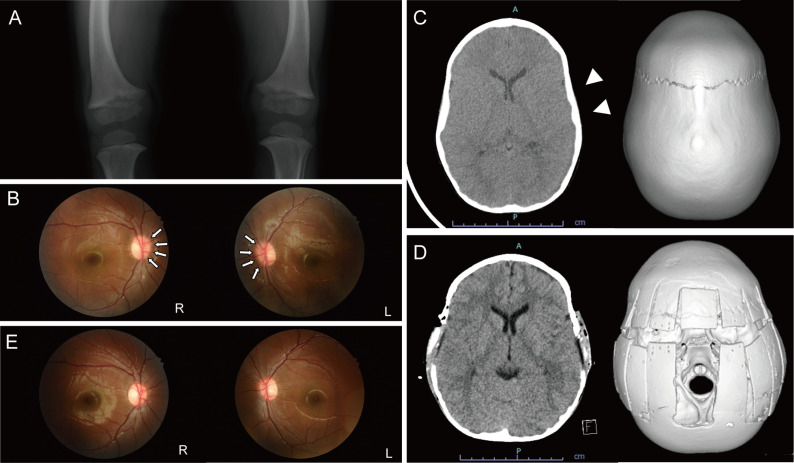

Significance of assessing the severity of craniosynostosis in patients with X-linked hypophosphatemia (XLH) at diagnosis.